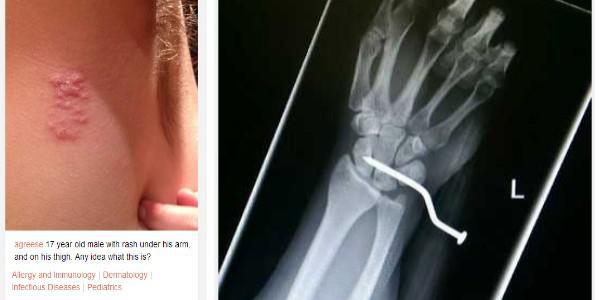

©Figure1

Pour recueillir les avis d'autres spécialistes, des médecins postent des photos de leurs patients présentant des symptômes peu communs sur une nouvelle application smartphone.

Depuis le 3 décembre, les médecins français peuvent demander conseil à leurs confrères en direct, grâce à l'application "Figure 1". Surnommée "l'Instagram des médecins", cette dernière permet aux professionnels de santé de poster des images médicales et d'échanger sur les diagnostics possibles. C'est en menant une étude auprès de ses collègues que le Dr Josh Landy, co-fondateur de l'application, a eu l'idée de créer "Figure 1". Interrogé par l 'Obs, il raconte avoir découvert que 13% des médecins partagent les photos de cas étranges. Sur l'application, on peut ainsi trouver le cliché d'un jeune homme avec des boutons sous l'aisselle ou d'autres un peu plus durs à regarder.